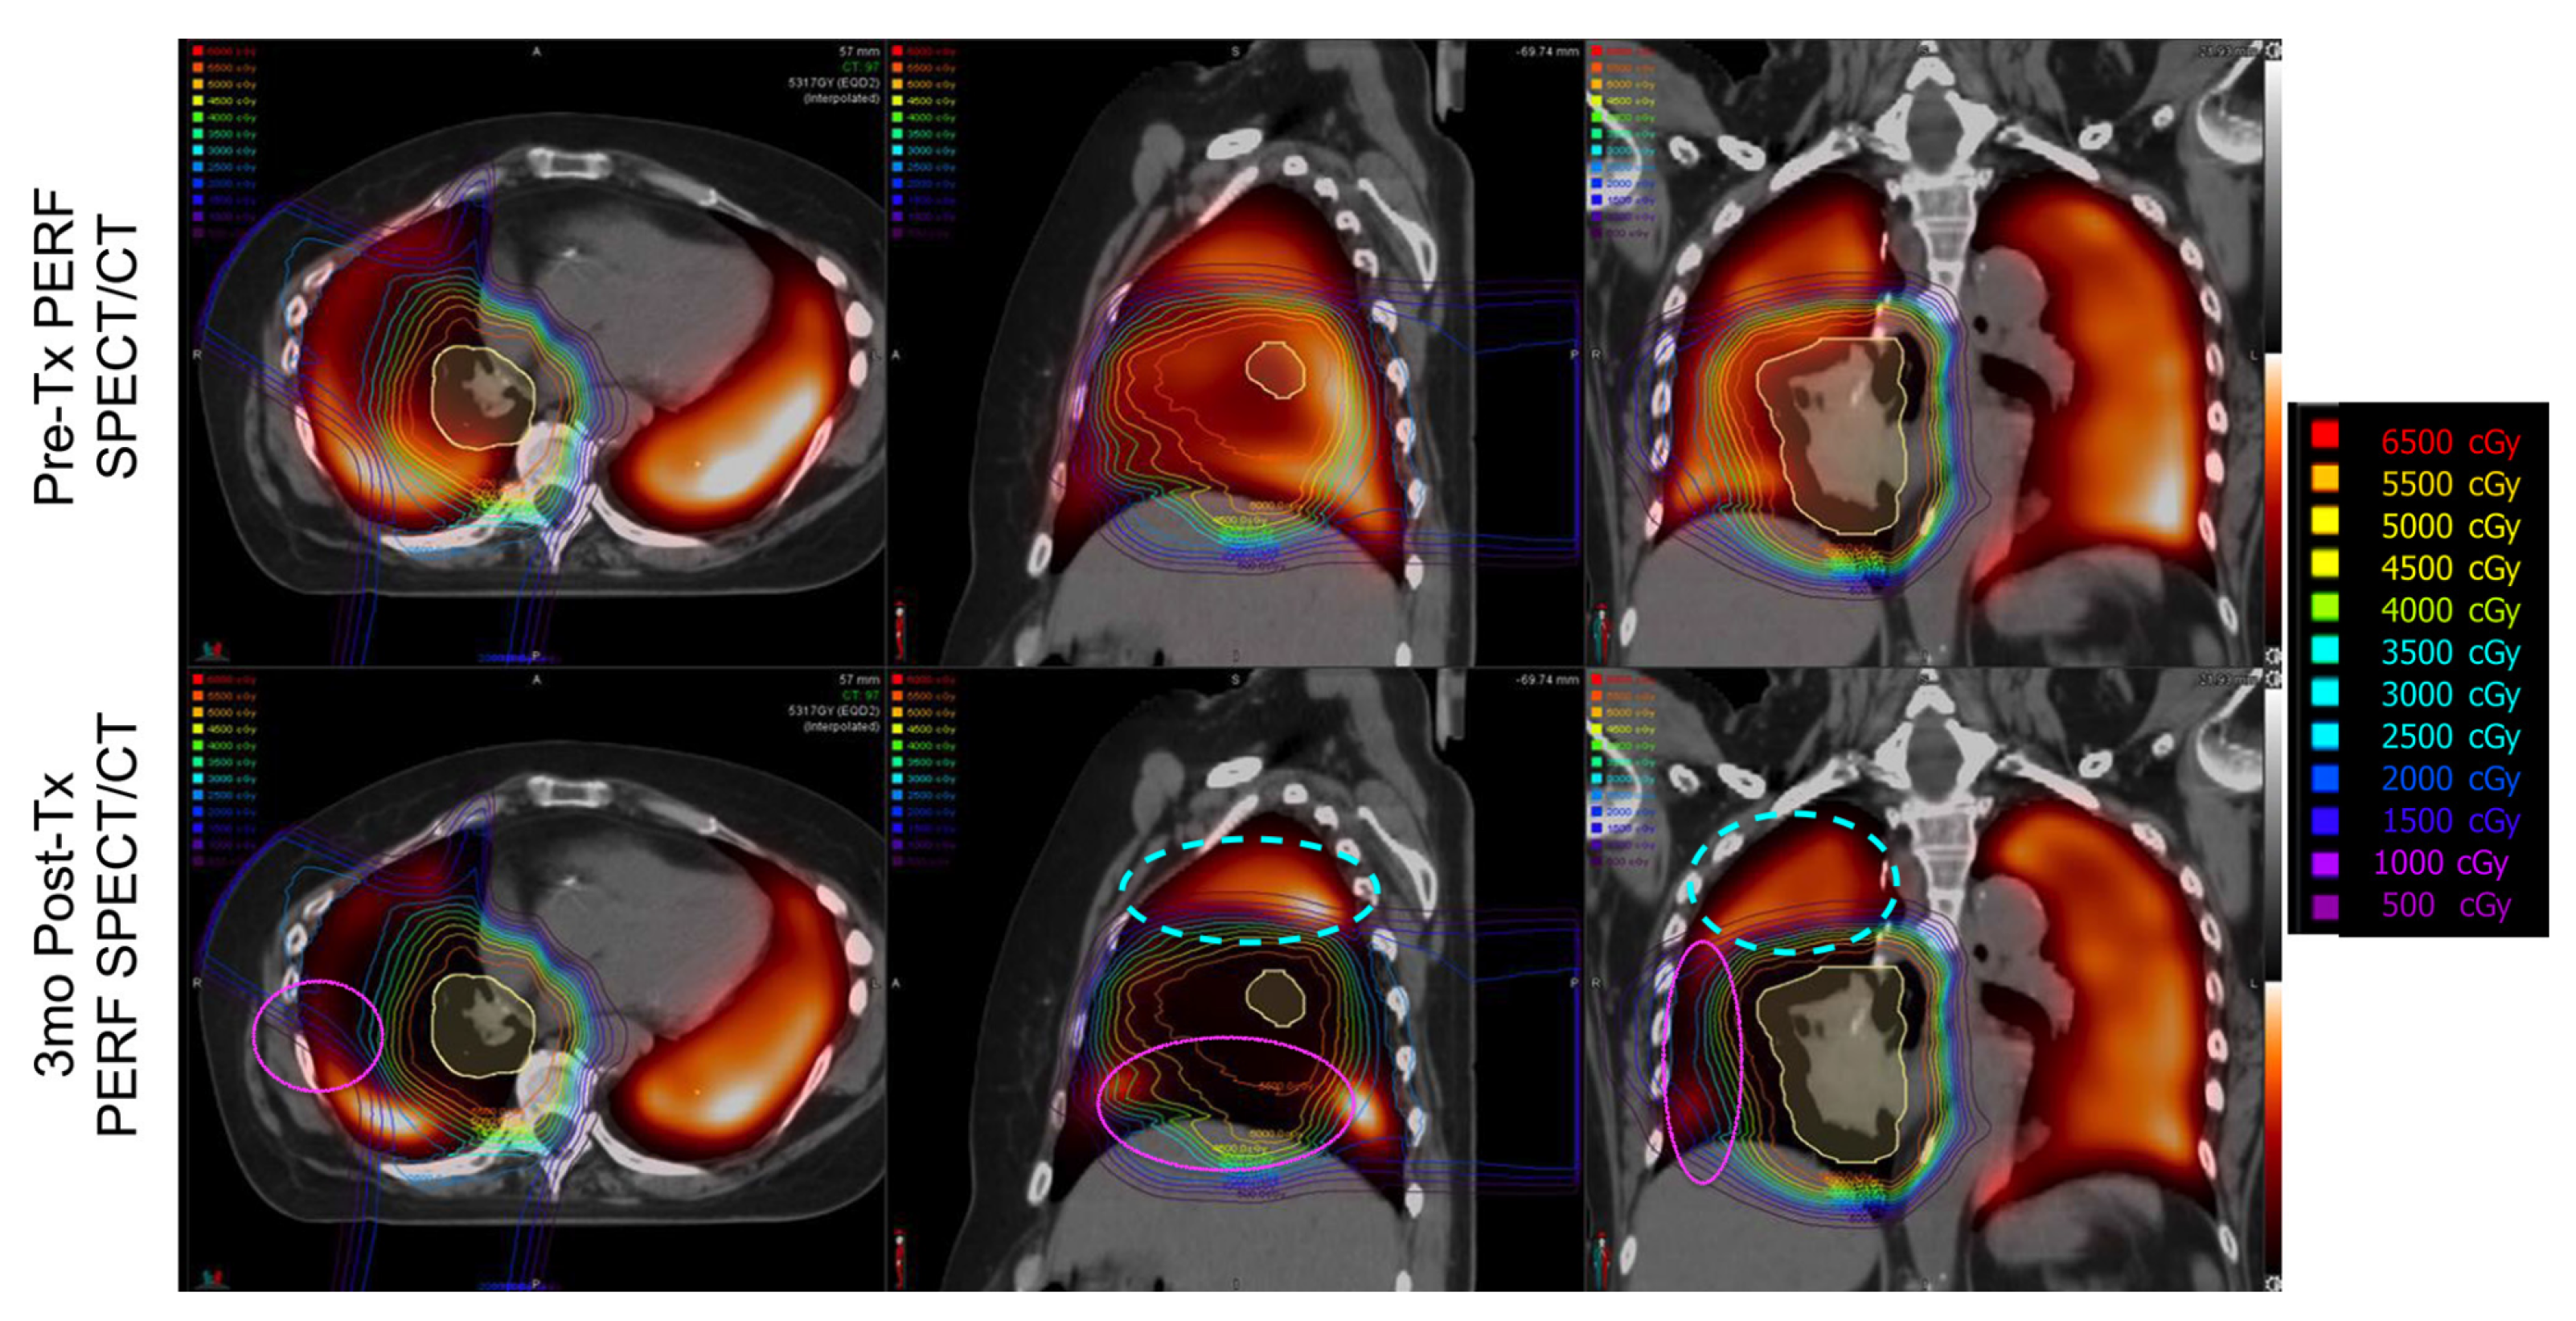

Imaging Results